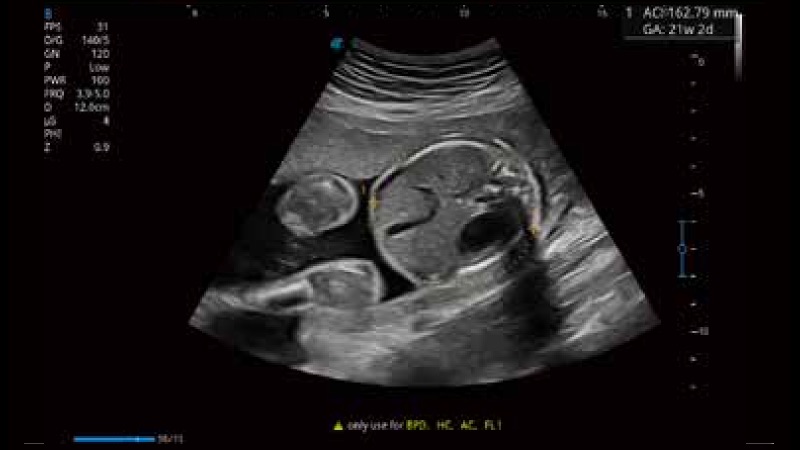

凭借狗万官方网站先进的成像技术和优异的探头技术提供的清晰的图像表现,您可以更自信地做出临床决策。